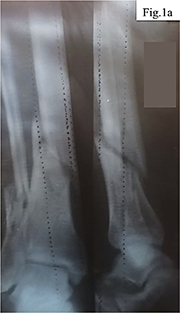

Clinical case. The patient, a 40-year-old man, sustained an injury to the right tibia as a result of tripping over a tree stump while carrying firewood. His medical history included a cervical spine injury after diving into shallow water, which may indicate increased vulnerability to traumatic loads. Initial examination and radiography revealed a closed comminuted fracture of the tibia with intramedullary fragments (Fig. 1).

Considering the nature of the fracture and the need for stable fixation of the fragments, a decision was made to perform open osteosynthesis using metal plates, as shown in Figure 2. The surgical treatment was delayed for two weeks due to implant supply interruptions associated with the military conflict in Ukraine. During the operation, two metal plates with a total of 16 screws were implanted, the wound was closed in layers, and four drains were placed to control postoperative fluid outflow.